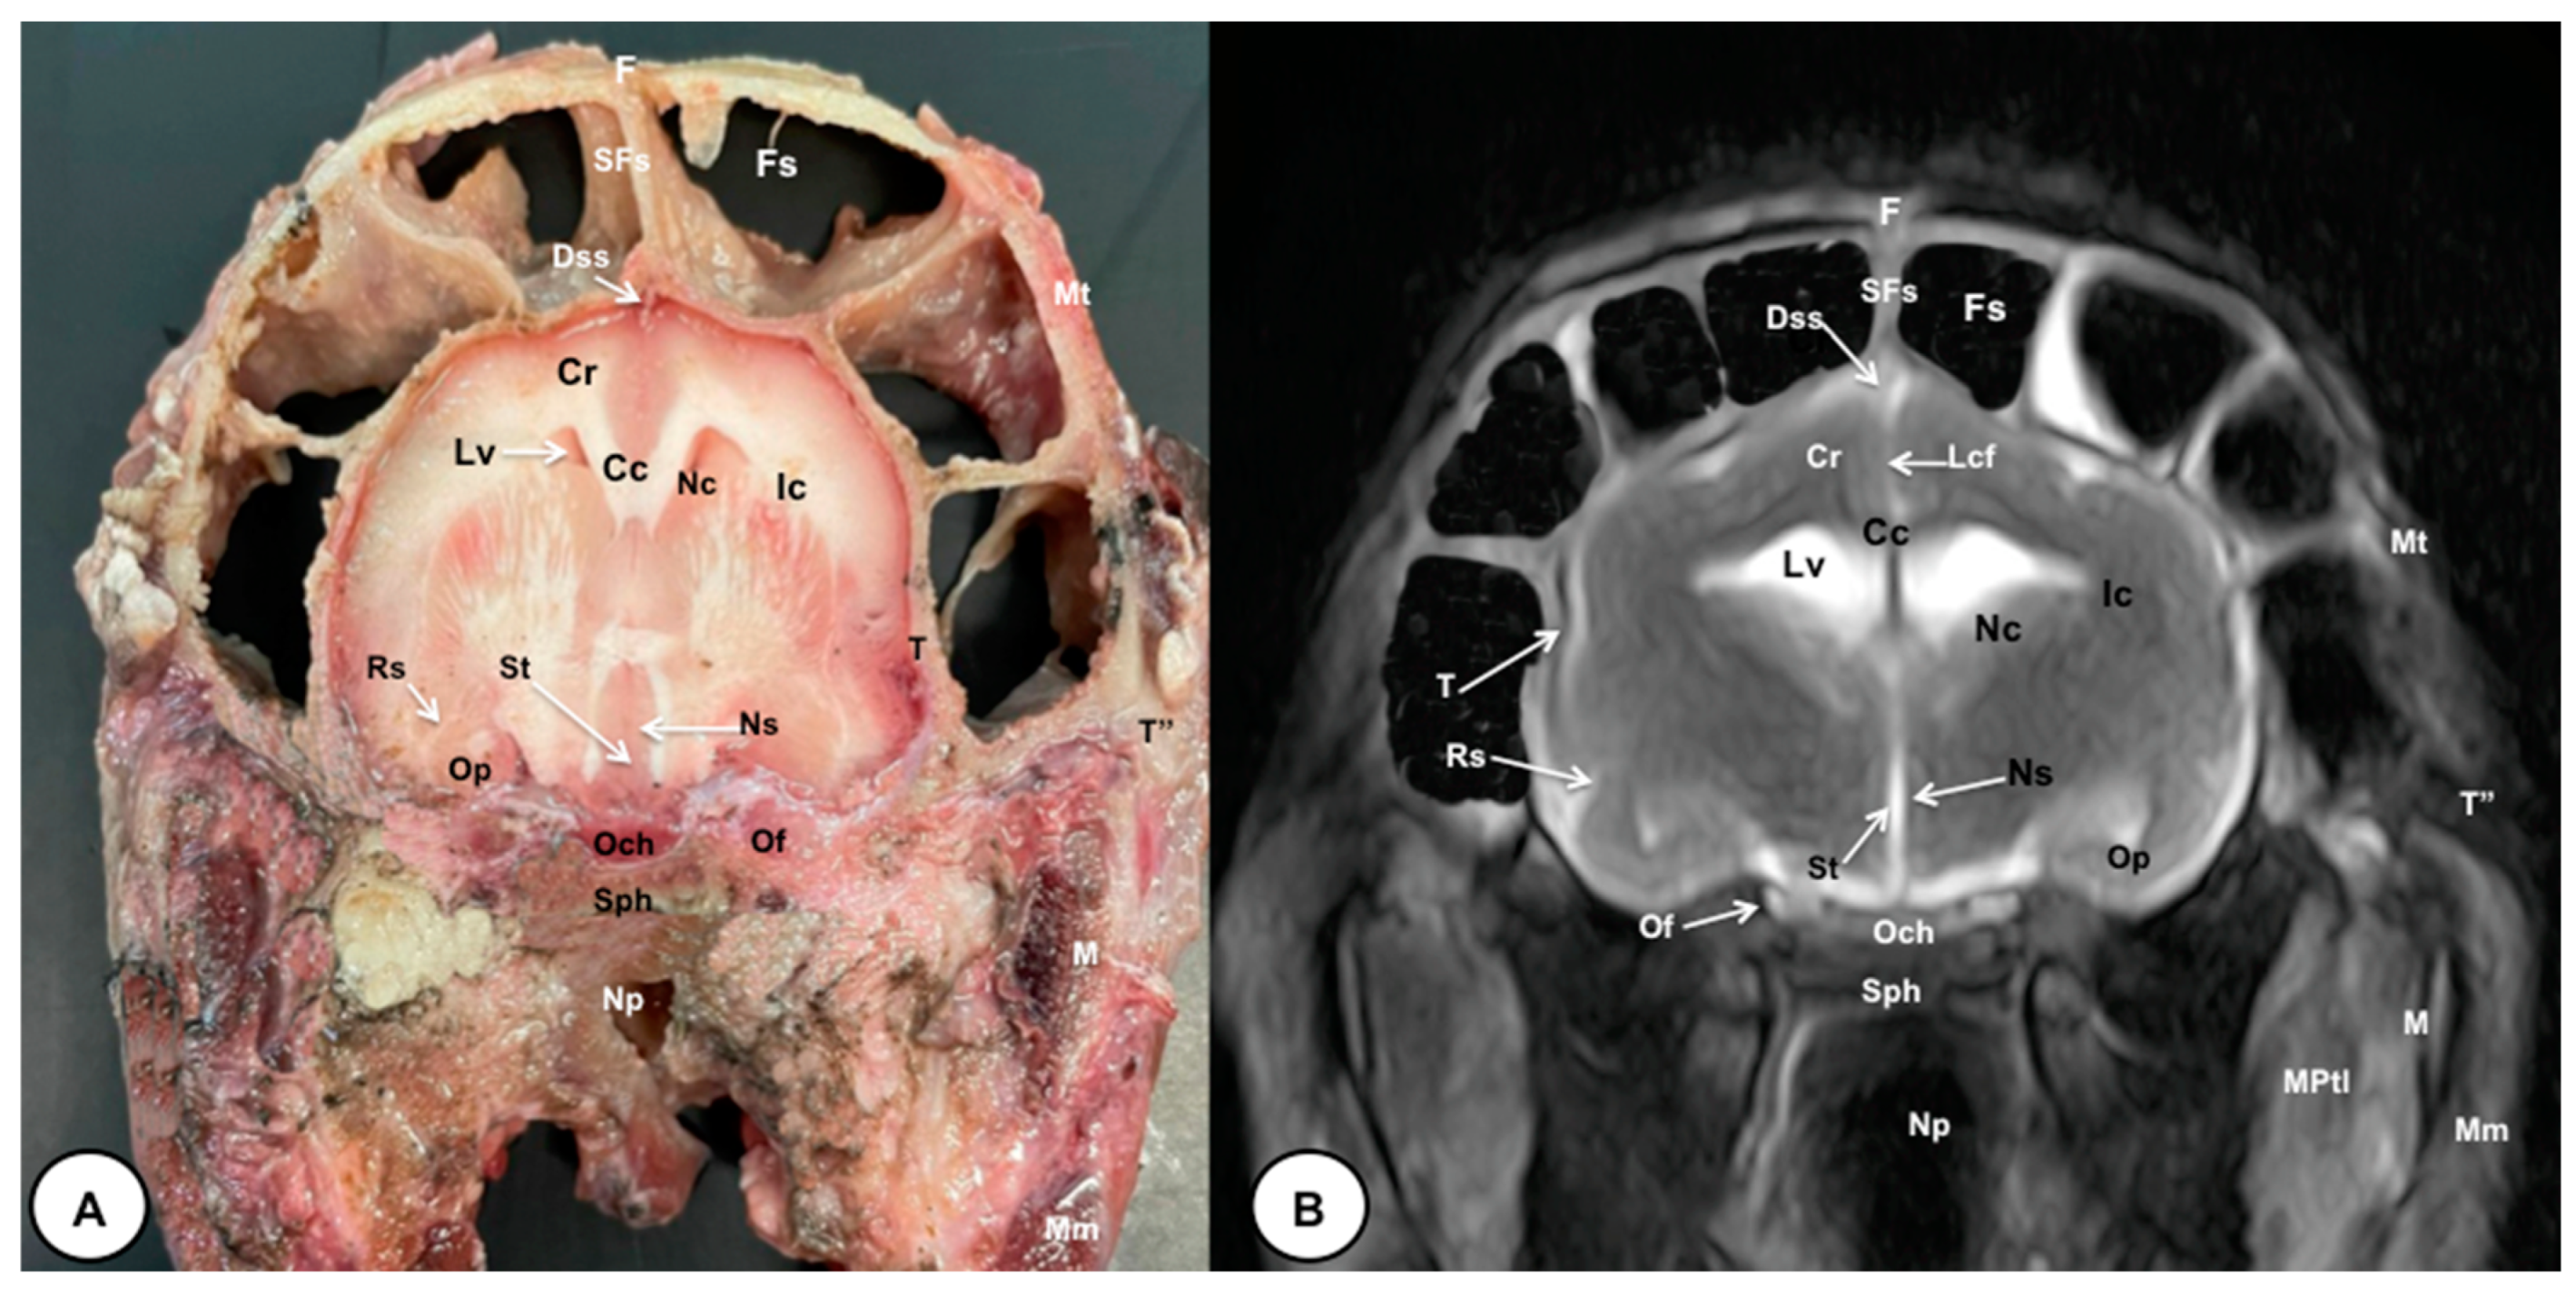

Figure 4.

Transverse cross-section (A) and T2W MR (B) images of the crested porcupine head at the level of the optic chiasm, corresponding to line III in Figure 1. F: frontal bone; Fs: frontal sinuses; SFs: septum of frontal sinuses; Dss: dorsal sagittal sinus; Lcf: longitudinal cerebral fissure; Cc: corpus callosus; Cr: Corona radiata; Lv: lateral ventricle; Nc: Nucleus caudatus; Ic: internal capsule; Rs: rhinal sulcus; Op: olfactory peduncle; St: septum of telencephalon (Septum telencephali); Ns: Nuclei septi; Och: optic chiasm; Of: orbital fissure; T: temporal bone (squamous part); T″: zygomatic process of temporal bone; Sph: sphenoid bone; Np: nasopharynx; Mt: Musculus temporalis; MPtl: Musculus pterygoideus lateralis; M: mandible. Mm: Musculus masseter.

The anatomical sections obtained in this study allowed us to visualize the different structures belonging to the central nervous system and its associated structures, which were labeled according to the International Committee on Veterinary Gross Anatomical Nomenclature. Therefore, we identified the main components of the brain (the prosencephalon, mesencephalon, and rhombencephalon). Thus, the two telencephalic hemispheres surrounded by the cerebral cortex and separated by the longitudinal cerebral fissure were identified (Figure 5A, Figure 6A and Figure 7A). Both hemispheres were connected by fibers of white matter known as the corpus callosum (Figure 4A, Figure 5A, Figure 6A and Figure 7A). Each cerebral hemisphere contained a lateral ventricle (Figure 4A, Figure 5A, Figure 6A and Figure 7A). Ventrally, we distinguished a component of the basal ganglia, the nucleus caudatus (Figure 4A and Figure 5A). Thus, we identified different parts of it, such as the head and the tail. Other structures which we observed were the septal nuclei, which were circumscribed by two parallel vertical lines through the most inferior and medial aspect of each lateral ventricle (Figure 4A). More caudally, the diencephalon enclosing the third ventricle was identified, as well as more ventrally specific components of the hypothalamus, such as the optic chiasm (Figure 4A and Figure 5A). Additionally, these sections were quite helpful in showing the caudal parts of the thalamus. Hence, the lateral eminence on the caudodorsal surface of the thalamus, known as the lateral geniculate body, was distinguished, whereas caudoventrally, we identified the medial geniculate body of the thalamus (Figure 5A). Moreover, the dorsal part of the mesencephalon with the caudal and rostral colliculus and its ventral part with the cerebral peduncles were also shown (Figure 6A and Figure 7A). These anatomical sections were helpful in identifying the vermis and the cerebellar peduncles, which connected the cerebellum to the adjacent brain stem and the cerebrum (Figure 7A). The ventral part of the cerebellum with the lingula, covering part of the fourth ventricle, could also be identified (Figure 7A). These sections were also helpful in distinguishing the medulla oblongata and the decussation of the pyramids. In addition, different bony structures comprising the neurocranium were observed, such as the frontal, the temporal (with its scamous, petrous, and tympanic parts), the sphenoid, and the occipital bones (Figure 2A, Figure 3A, Figure 4A, Figure 5A, Figure 6A and Figure 7A). Furthermore, these sections showed different air-filled spaces, such as the frontal and the sphenoidal sinuses (Figure 2A, Figure 3A, Figure 4A, Figure 5A, Figure 6A and Figure 7A), and structures associated with the nasal cavity, including the ethmoturbinates and the vomer, could be distinguished (Figure 2A and Figure 3A). Main sensory organs such as the eyeball and its associated structures were also depicted. Consequently, we identified the retina, the vitreous chamber, and the optic nerve, which were surrounded by extraocular muscles. Among these, we distinguished the dorsal and ventral rectus muscles (Figure 2A). Moreover, the main components of the auditory system, such as the external auditory canal, the tympanic cavity, and the inner ear, were visualized (Figure 5A and Figure 6A). Also, we identified the relevant muscles related to masticatory function, such as the temporalis, the medial and lateral pterygoid muscles, the masseter, the digastric muscle, and other important muscles, including the buccinator muscle and the longissimus capitis of the head (Figure 2A, Figure 3A, Figure 4A, Figure 5A, Figure 6A and Figure 7A).

No significant anatomic differences were identified subjectively in the three porcupines which were imaged. Most anatomic structures distinguished on T2-weighted images of the cadaver specimens matched adequately with structures identified in the corresponding anatomical cross-sections. Hence, the central nervous system structures of the porcupine head, the eyeball’s structures (vitreous humour and lens), and the masticatory muscles showed an accurate visualization using T2W MR images. Nonetheless, the bones that comprised the neurocranium, such as the frontal, the parietal, the temporal, the occipital, and the sphenoid bones, were identified with a hypointense signal (Figure 2B, Figure 3B, Figure 4B, Figure 5B, Figure 6B, Figure 7B, Figure 8 and Figure 9).

In the transverse planes of the encephalon, identifiable structures of the brain were more hyperintense than the white matter, which was more hypointense in T2W sequences (Figure 3B, Figure 4B, Figure 5B, Figure 6B and Figure 7B). Moreover, the two sagittal and dorsal (Figure 8 and Figure 9) images and the different transverse T2W images were essential to depicting the components that comprise the ventricular system, which displayed a hyperintense signal. Hence, the lateral ventricles and the dorsal and ventral parts of the third ventricle were displayed (Figure 4B, Figure 5B, Figure 6B, Figure 7B, Figure 8 and Figure 9), and among these, we observed interthalamic adhesion, limited laterally by the right and left sides of the thalamus (Figure 8A). In addition, transverse, sagittal, and parasagittal T2W images displayed with adequate detail the dorsal and ventral parts of the hippocampus (Figure 5B, Figure 6B, Figure 7B, Figure 8B and Figure 9). In addition, the tectum of mesencephalon (tectum mesencephali) with the caudal colliculus and the fourth ventricle was visualized in excellent detail (Figure 8A,B and Figure 9B). Other essential components of the CNS, such as the vermis of the cerebellum with its dorsal and ventral lobes, were distinguished in the sagittal T2W images (Figure 8A). Hence, the moderate contrast between grey and white matter was helpful in distinguishing the different lobes. Thus, the dorsal lobes of the cerebellum (the rostral and ventral culmen, the declive, the folium, the tuber, and the pyramid), as well as its ventral lobes (the lingula, the nodulus, and the uvula), were identified. In addition to these findings, we also observed the rostral and caudal cerebellar peduncles (Figure 7B and Figure 9A). This technique also facilitated an adequate resolution to be achieved with which to identify the muscles involved in the masticatory function, which have already been mentioned in the anatomical sections.